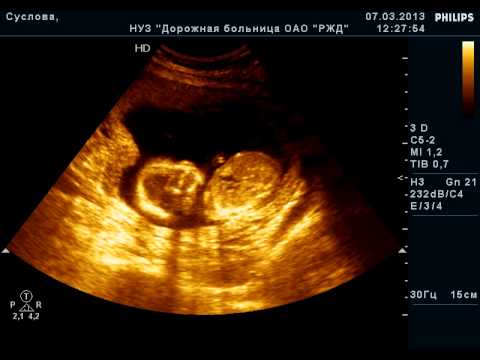

Беременность 15 Недель Развитие Фото

Беременность 15 Недель Развитие Фото 115 фото